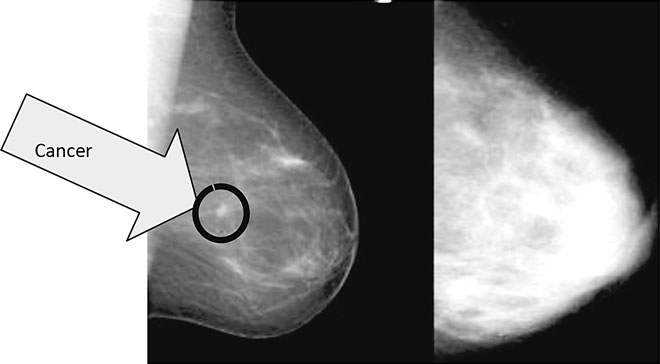

In 2013 the Lafayette woman who never misses her annual doctor’s visit with OB-GYN Daniel Bourque had no lumps and a clean mammogram. What she did have was dense breast tissue, which nearly hid the minute cancer from view.

“My mammogram was clear, [but] the ultrasound showed [the cancer],” John says.

Chances are great that you just might be dense — in your breasts. Dense breast tissue is comprised of less fat and more connective tissue, which appears white on a mammogram. Cancer also appears white, which makes spotting cancer in dense breast tissue more challenging than in fatty tissue.